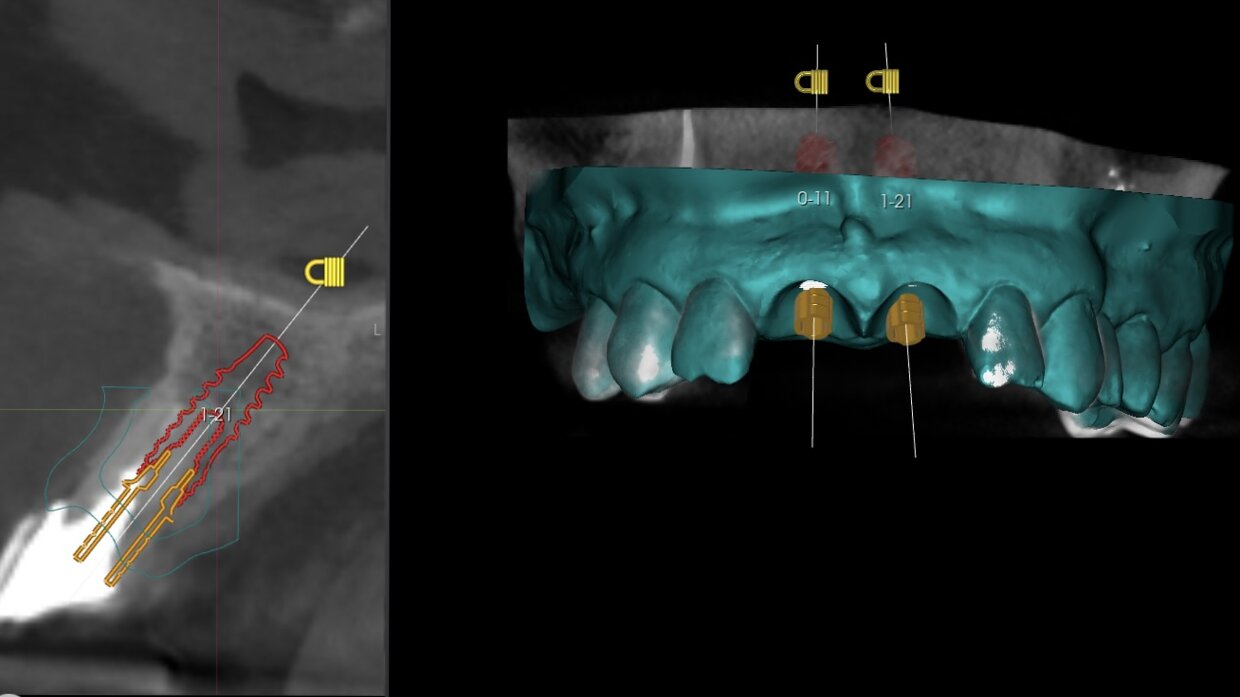

Il posizionamento degli impianti è stato pianificato prima dell'intervento su un software dedicato. In un'unica seduta, dopo l'estrazione degli elementi dentari compromessi, sono stati immediatamente inseriti gli impianti nella posizione pianificata, grazie alla realizzazione della dima chirurgica. Per ridurre il riassorbimento osseo a lungo termine e garantire quindi una maggiore resa estetica (vista la zona d'intervento), la chirurgia è stata eseguita con una particolare tecnica denominata: Socket Shield Technique.

Scopri quali sono i passaggi per la pianificazione digitale degli impianti